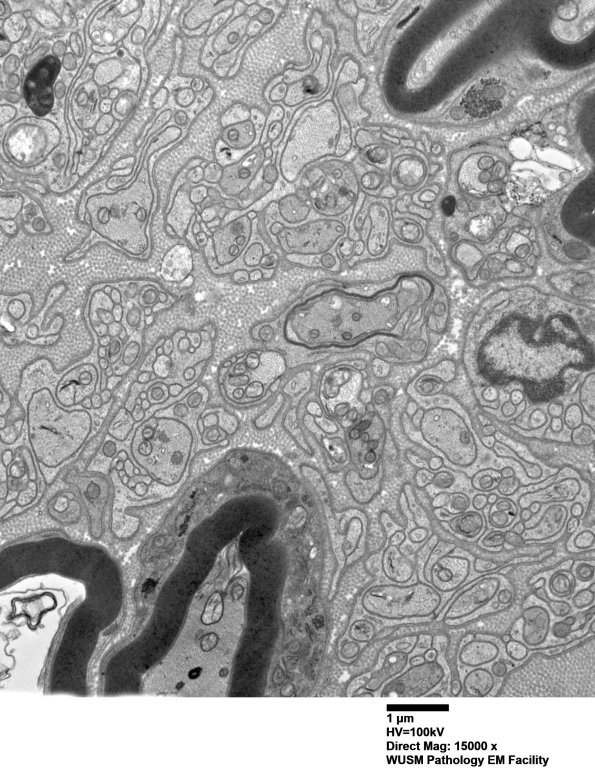

Washington University Experience | PERIPHERAL NEUROPATHY | 1 NORMAL NERVE ANATOMY | 6 Infant Peripheral Nerve | 2B10 W20-132 A (Case 2) tibial_014 - Copy

Additional thinly myelinated developing axons are identified. (electron micrograph)